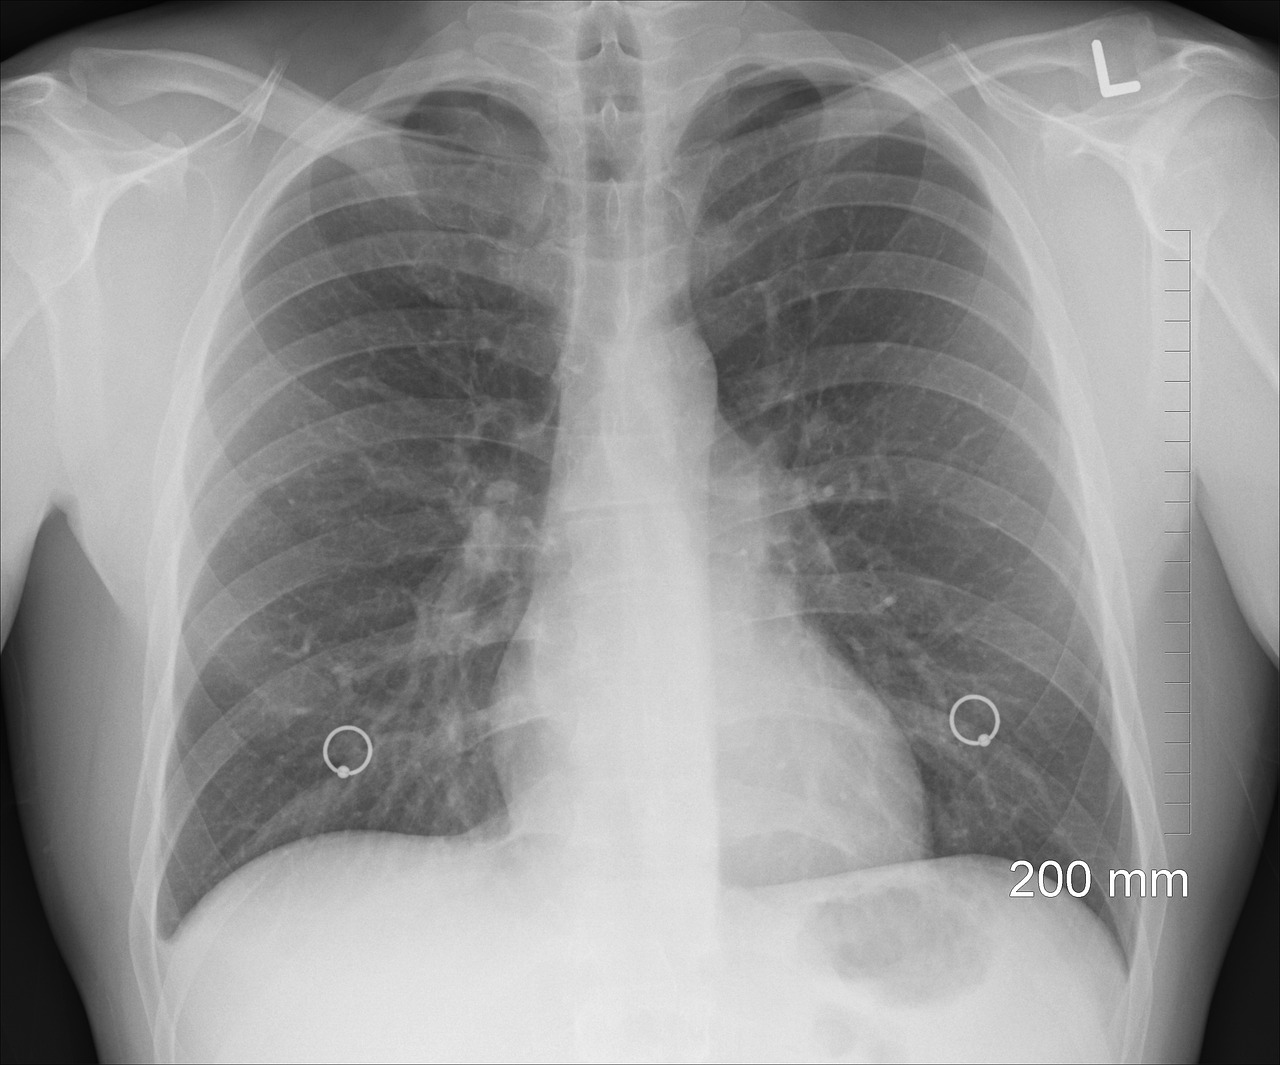

많은 사람들이 나이가 들면서 숨이 차는 증상을 단순한 노화로 여깁니다. 하지만 이런 증상이 지속된다면 '만성 폐쇄성 폐질환(COPD)'을 의심해볼 필요가 있습니다. 이 질환은 천천히 진행되면서 폐 기능을 떨어뜨리고, 심할 경우 산소 공급이 어려워지는 심각한 상태로 발전할 수도 있습니다.

COPD는 폐로 들어가는 공기의 흐름이 지속적으로 제한되는 만성 호흡기 질환입니다. 주요 원인은 흡연이지만, 대기 오염, 직업적인 유해 물질 노출, 유전적인 요인도 영향을 미칠 수 있습니다.

COPD는 조기 진단이 어렵기 때문에 초기 증상을 가볍게 넘기지 말고 병원을 방문해 검사를 받아야 합니다.

COPD는 조기 진단이 중요합니다. 특히 40세 이상이고 흡연 경험이 있다면 폐 기능 검사를 정기적으로 받는 것이 필요합니다. 폐활량 측정을 통해 폐 기능 저하 여부를 확인할 수 있으며, 조기 발견 시 적절한 치료를 통해 악화를 막을 수 있습니다.